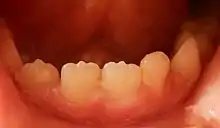

Mamelons on the lower central and lateral right incisors of a seven-year-old boy

A mamelon (from French mamelon, "nipple") is one of three rounded protuberances which are present on the cutting edge of an incisor tooth when it first erupts through the gum. Mamelons' appearance can be smoothed by a dentist if they have not been worn down naturally by biting and eating foods. [1]Mamelons are present on permanent central and lateral incisors. Mamelons are easiest to observe on the maxillary central incisors, and appear as three small prominences on the incisal edge of the tooth. Mamelons are ordinarily of no clinical importance. Usually they are worn off early in the life of the tooth. However, when an anterior open bite is present—that is, the anterior teeth are not in contact when the bite is fully closed—mamelons may remain into adulthood.